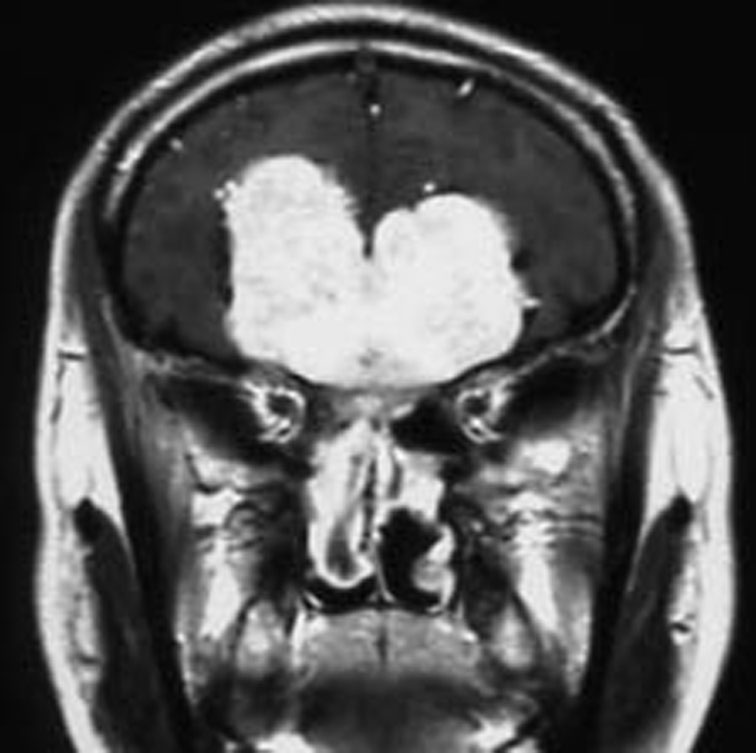

嗅窩髄膜腫 olfactory gloove meningioma

50代の女性が臭いと味がわからないという症状で発症しました。臭いが鈍くなると味が変わります。典型的な普通のサイズの嗅窩髄膜腫です。嗅覚脱失であり嗅索機能を温存することはできませんでした。

嗅窩髄膜腫 olfactory gloove meningioma(全頭蓋底を抜けるもの)

嗅窩を破って篩骨洞内(鼻腔)に抜けているものです。嗅神経芽腫 olfactory neuroblastoma, esthesioneuroblastoma と見分けがつかないようなものです。